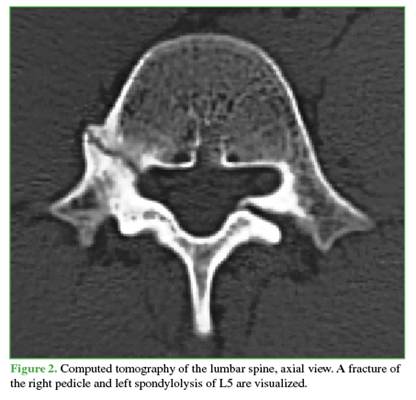

Anteroposterior, lateral, and oblique radiographs of the lumbar spine showed sclerosis of the right pedicle and left-sided spondylolysis at the level of the fifth lumbar vertebra. CT scan revealed, in addition to the findings mentioned above, a discontinuity in the right pedicle, with sclerotic and hypertrophic margins (Figures 1 and 2). Magnetic resonance imaging demonstrated edema in the lumbar pedicle (Figures 3 and 4).

A common feature of pediculolysis is sclerosis of the pedicle, although it remains unclear whether this represents an adaptive phenomenon prior to the fracture or a consequence of it.9 This unilateral sclerosis gives the vertebra an asymmetric appearance on radiological imaging. Computed tomography (CT) undoubtedly allows for better assessment of the lesion, differential diagnosis, monitoring of progression, and, in some cases, therapeutic planning. Characteristic CT findings include a radiolucent line of discontinuity with sclerotic and hypertrophic margins.4 Magnetic resonance imaging (MRI) has high sensitivity for diagnosing these lesions. While it may or may not reveal the fracture line at the pedicle level, it does demonstrate associated edema, which appears hypointense on T1-weighted sequences and hyperintense on T2-weighted sequences.3,4